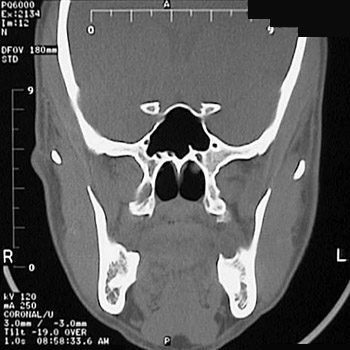

This is a normal sinus CT scan demonstrating the sphenoid sinus and nasopharynx and mandible in the skull.